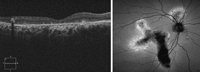

La sospecha diagnóstica de la CSC es eminentemente clínica, y suele confirmarse mediante angiografía fluoresceínica y OCT (

Figura 1). Recientemente, nuevos estudios con verde de indocianina y el desarrollo de nuevas OCT que permiten un mejor estudio de la coroides han relevado claves que hacen pensar en un origen coroideo de la enfermedad

Figura 1. Coroidorretinopatía serosa central aguda en ojo derecho. Se objetiva punto de fuga en la angiografía fluoresceínica y desprendimiento neurosensorial de la retina.